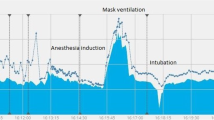

Postoperative pulmonary complications (PPCs) after major surgery and general anaesthesia are an important cause of morbidity and mortality in the perioperative setting [1]. To minimize such adverse events, it is crucial to identify predisposing conditions [2] and assess the underlying pathophysiology to provide a lung protective ventilation strategy [3, 4]. Ventilatory monitoring in the operating room is routinely based on the analysis of pressure, volume, and flow data provided by the ventilator [3, 5,6,7,8].

However, perioperative medicine has advanced, allowing for a broader array of surgeries on patients with serious health issues, such as extreme obesity or critical injuries. These include complex procedures like extended robotic surgeries in extreme positions or prolonged one-lung ventilation. Additionally, technological advancements provide new tools to monitor patients' physiological responses in real-time.

Currently, we can perioperatively employ devices such as electrical impedance tomography (EIT) that analyses lung regional ventilation [9], oesophageal pressure (Pes) monitoring which reflects approximately the pleural pressure, allowing transpulmonary pressure (Ptp) estimation [10], and lung and diaphragmatic ultrasound (US) that enable us to assess the echogenicity of the different lung fields to quantify aeration [11] or to assess diaphragmatic functionality [12]. This raises the question of whether and when these advanced respiratory monitoring tools should be used to prevent PPCs.

Monitoring of Ventilatory Mechanics Through Common Ventilatory Parameters Analysis

Conventional data such as pressure and flow curves or capnography can be leveraged to gain further insight into respiratory mechanics [13], helping us to assess the recruitment capacity and adequacy of patient ventilation [13, 14]. For instance, lung hysteresis, a physiological feature resulting from the visco-elastic properties of lung parenchyma, causes the pressure–volume relationship to differ between inflation and deflation [15, 16]. It can be quantified by the area enclosed within the quasi-static Pressure–Volume (PV) loops generated during mechanical ventilation [13]. These PV loops reveal a critical point where a sharp increase in ventilator pressure corresponds with a slower rise in lung volume, signaling the end of lung recruitment which could include some overdistension, whereas a pressure drop paired with a slower volume decrease indicates the onset of alveolar collapse [13, 15, 16]. Understanding these patterns helps to assess lung recruitability, and identify risks linked to mechanical ventilation [13].

The dynamic pressure–time curve can also be used to assess respiratory mechanics. For instance, the stress index (SI) [17], that assesses the dynamic pressure–time curve during constant inspiratory flow to detect intratidal recruitment or hyperinflation. A threshold SI value of greater than 1.05 has shown a sensitivity of 0.88 and a specificity of 0.50 to indicate injurious ventilation, which was contrasted with aeration indices based on computed tomography in ARDS patients. The SI obtained from the ventilator indicates the SI of the respiratory system and correlates with the lung SI with reasonable accuracy [18, 19].

Furthermore, volumetric capnography (VCap) performs a continuous assessment of the respiratory dead space [20] using the modified Bohr equation, which includes the tidal volume (VT), the partial pressure of CO2 at the end of alveolar respiration and the partial pressure of CO2 at the end of expiration (EtCO2) [21]. VCap divides the capnogram into three phases: Phase I, representing the CO2-free exhaled gas from the airways; Phase II, where a mix of airway and alveolar gases is present; and Phase III, which represents the alveolar plateau where gas exchange occurs. By separating the volume of gas in the airways from that within the alveolar compartment, it allows for precise calculations of dead space on a breath-by-breath basis. The slope of Phase III (SIII) is particularly informative as it reflects the ventilation-perfusion distribution in the alveoli. An increased slope indicates heterogeneity in alveolar ventilation. VCap is a current tool for clinical research works, proving to be an adequate guide in the assessment of end-expiratory lung volume (EELV) changes induced by surgical procedures and has proven to be useful in individualizing the level of PEEP during laparoscopic surgery [21, 22].